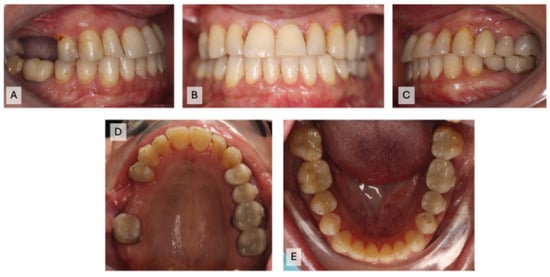

A 49-year-old Saudi female patient came to the orthodontic faculty clinics at Imam Abdulrahman bin Faisal University Dental Hospital with a complaint: “My teeth are crooked, and I would like to correct them”. Her medical history showed no significant findings. Her dental history showed multiple restorations and missing teeth. Upon clinical examination, multiple caries lesions, generalized calculus deposition, generalized gingival recession, a missing tooth (#3), two 3-unit FPDs on teeth #2, X, 4, & 13, X, 15, crowns on teeth #12, 19, 20, and 30, Class I malocclusion, an overjet range from 0 to 1 mm, a shallow overbite of 0–1 mm, a shifted lower midline of 1 mm, 3 mm upper crowding, and 1 mm lower crowding were found. The lateral cephalometric radiograph suggested a normodivergent pattern, with a Class III skeletal relation complicated by the retrognathic maxilla and proclined upper and lower incisors (Figure 1A–E and Figure 2A,B).

Figure 1.

The initial intraoral photographs before restorability assessments: (A) right occlusion; (B) front occlusion; (C) left occlusion; (D) maxillary occlusion; (E) mandibular occlusion.